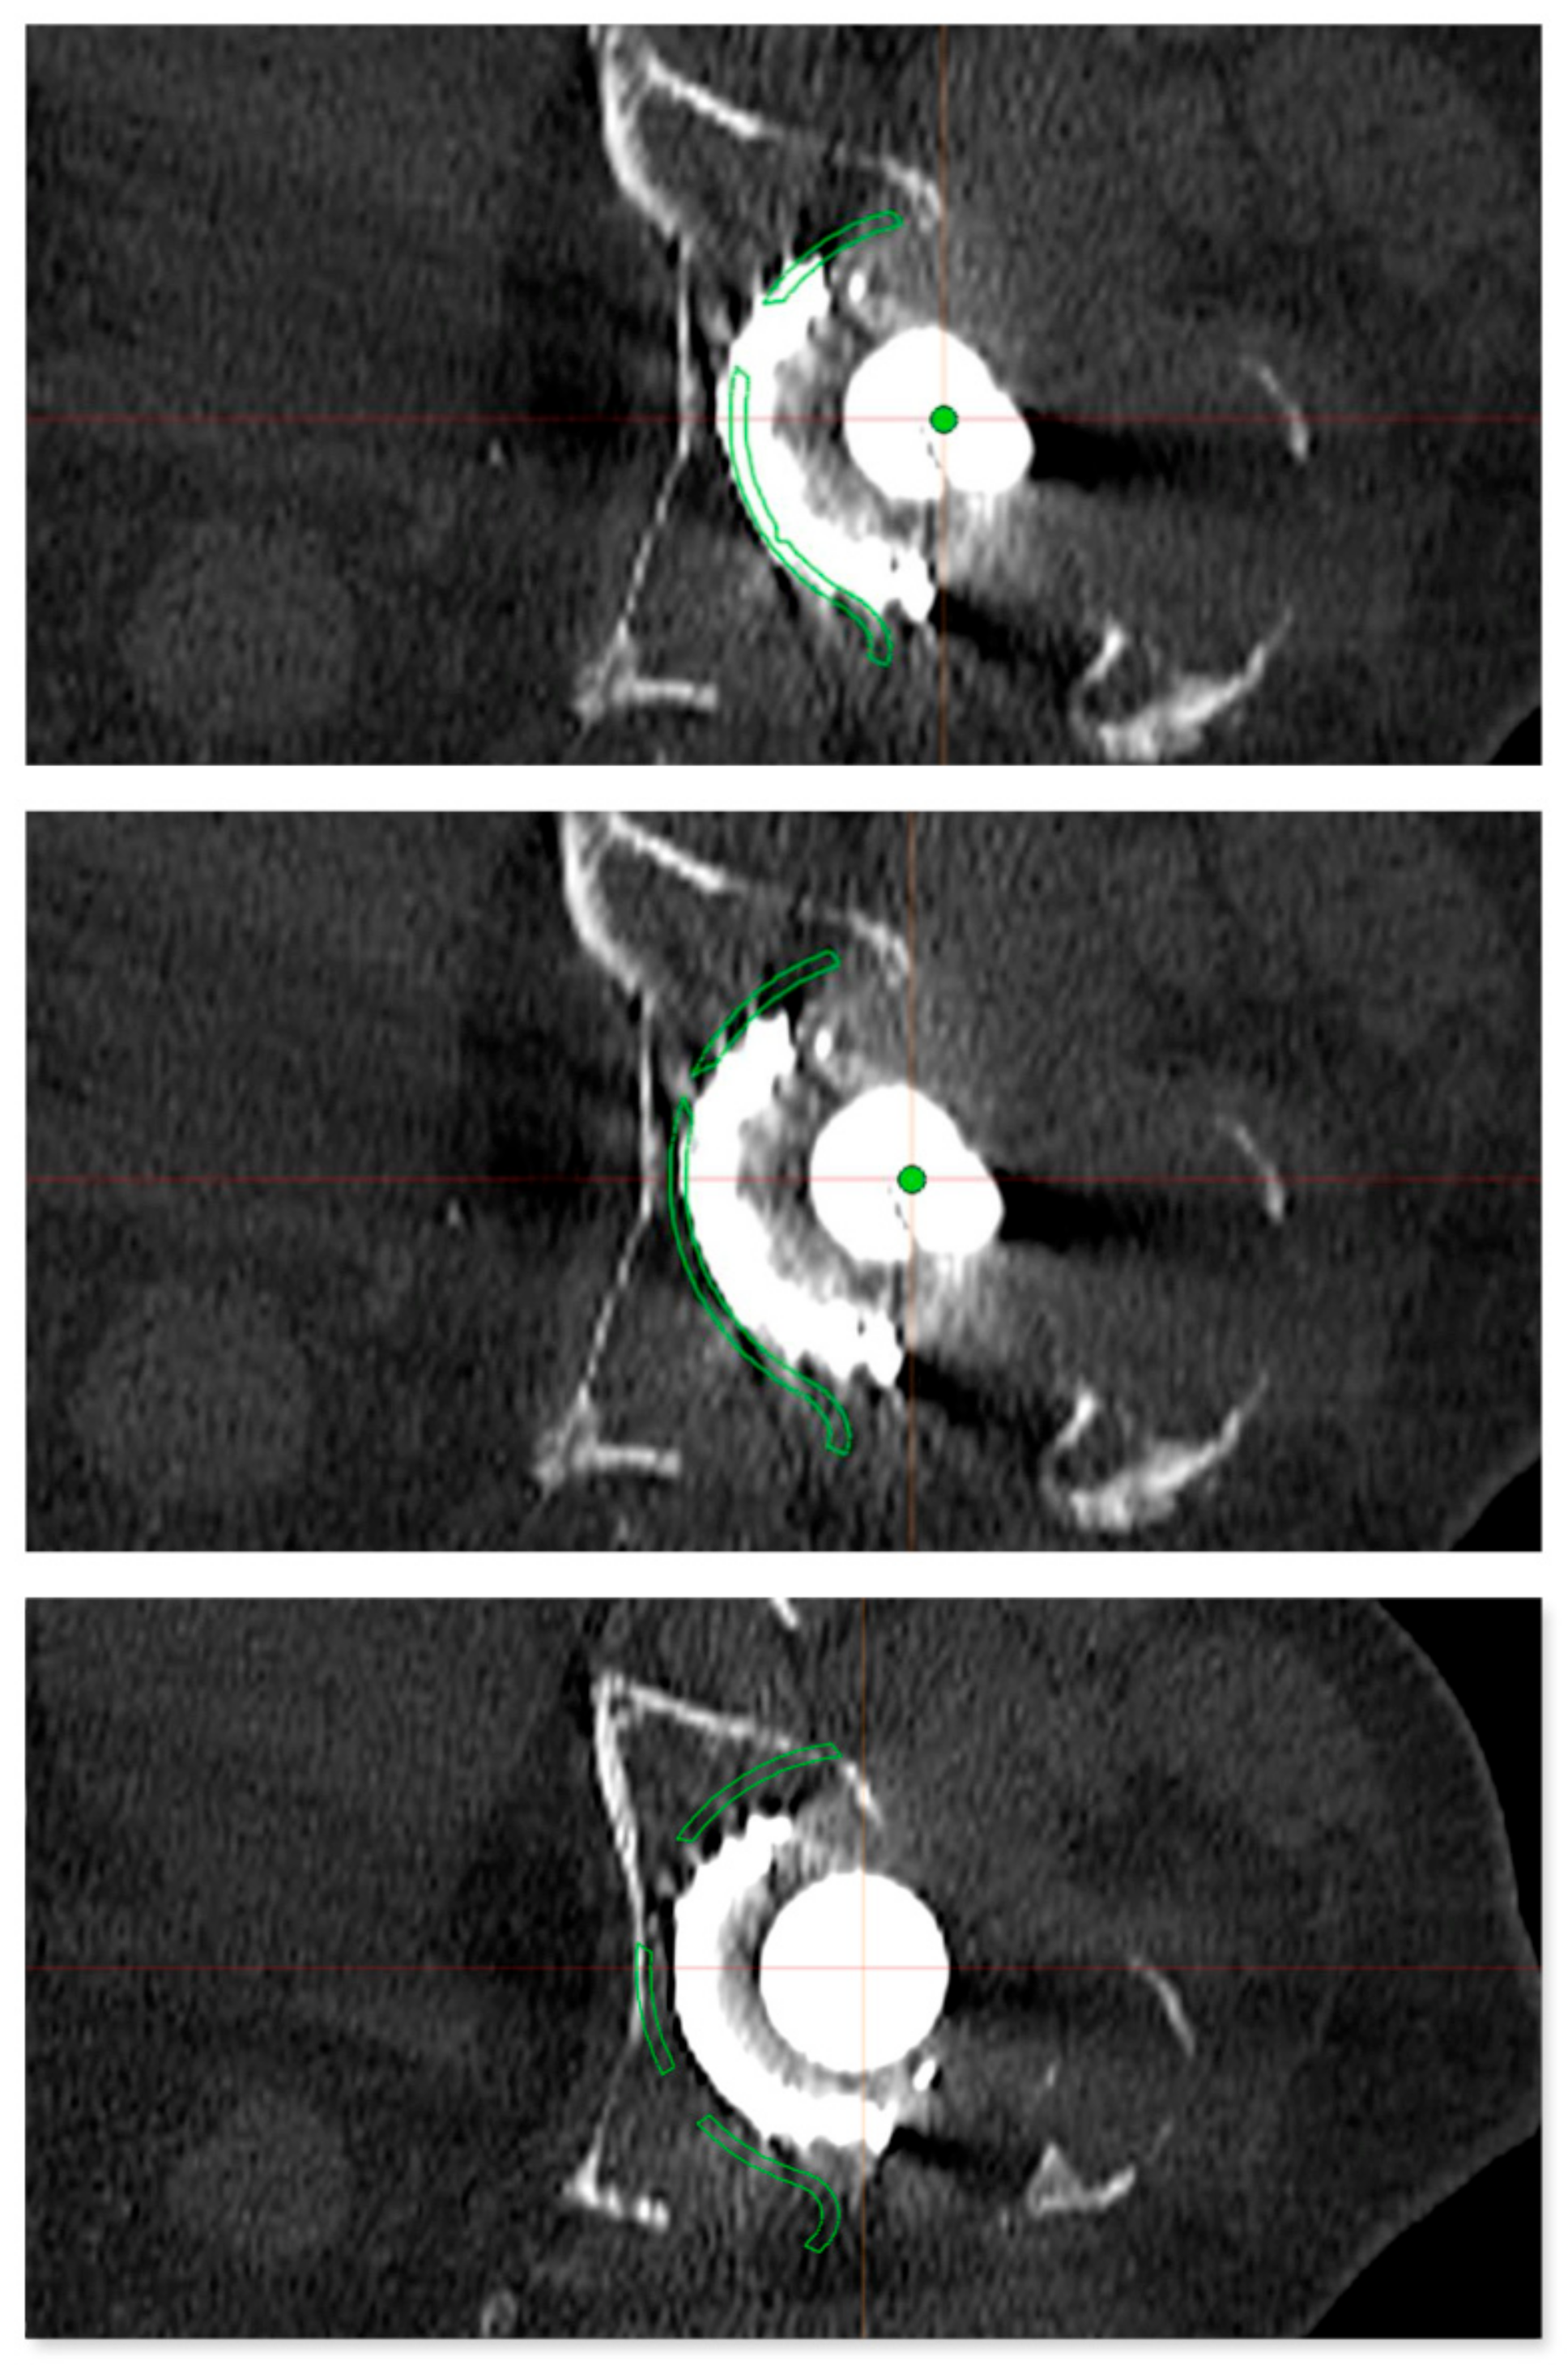

2.1. Preoperative Imaging

2.2. Digital Templating